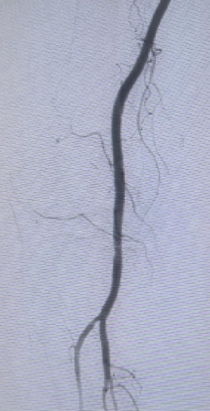

血管外科禄韶英主任及杨林副主任迅速协助组建手术团队,介入手术室、麻醉科、血管外科医护迅速响应,积极完善术前准备,凌晨1点,血管外科团队在局麻下为患者施行了左股动脉穿刺造影及吸栓导管取栓术。术中见右股腘动脉段血栓阻塞,经积极抽吸,大量新鲜血栓被清除,血流成功恢复。整台手术紧张有序,患者生命体征平稳,术后安返血管外科病房。